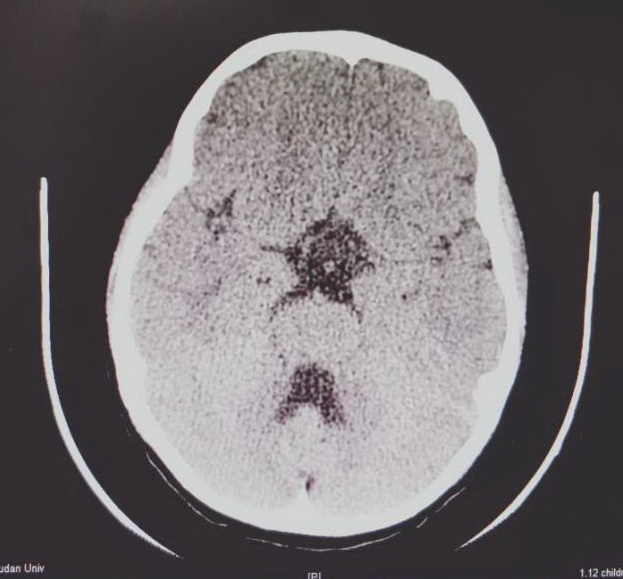

术后CT复查肿瘤被切除